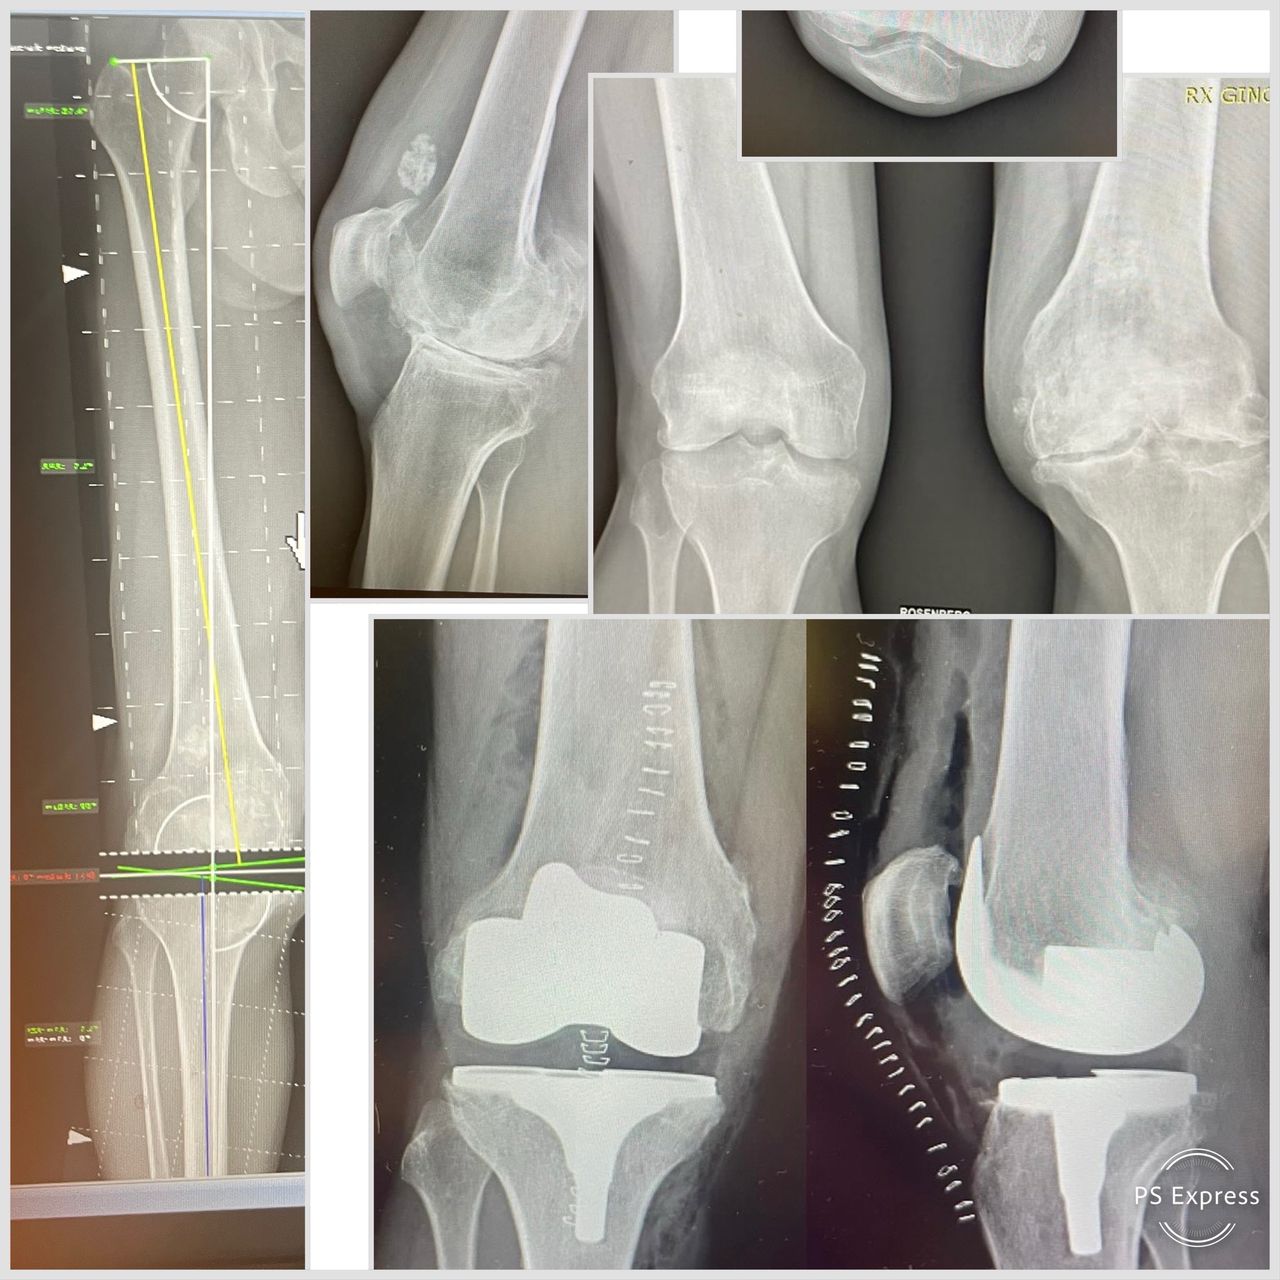

• Chirurgia protesica mini-invasiva di anca e ginocchio a Firenze – interventi eseguiti con approcci che riducono il trauma chirurgico, rispettano i tessuti e favoriscono un recupero più rapido.

• Planning pre-operatorio 2D e 3D – pianificazione computerizzata che assicura la massima precisione nella ricostruzione della biomeccanica articolare.